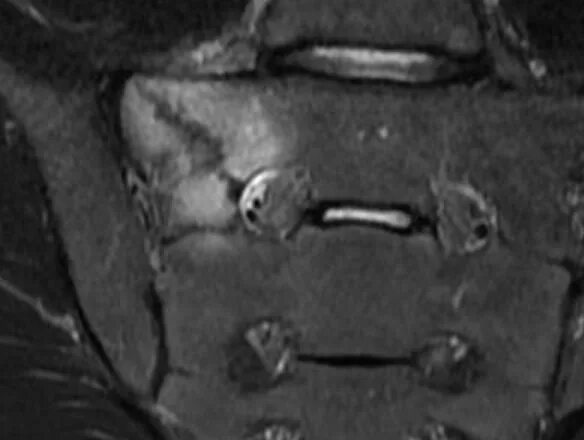

Стресс-перелом боковых масс крестца мрт. перелом боковых масс крестца.

Перелом крестцового отдела позвоночника. стресс-перелом боковых масс крестца мрт. перелом s3 позвонка крестца. перелом крестца позвонка s5.

Мрт крестцово-подвздошных сочленений. перелом копчика рентген.